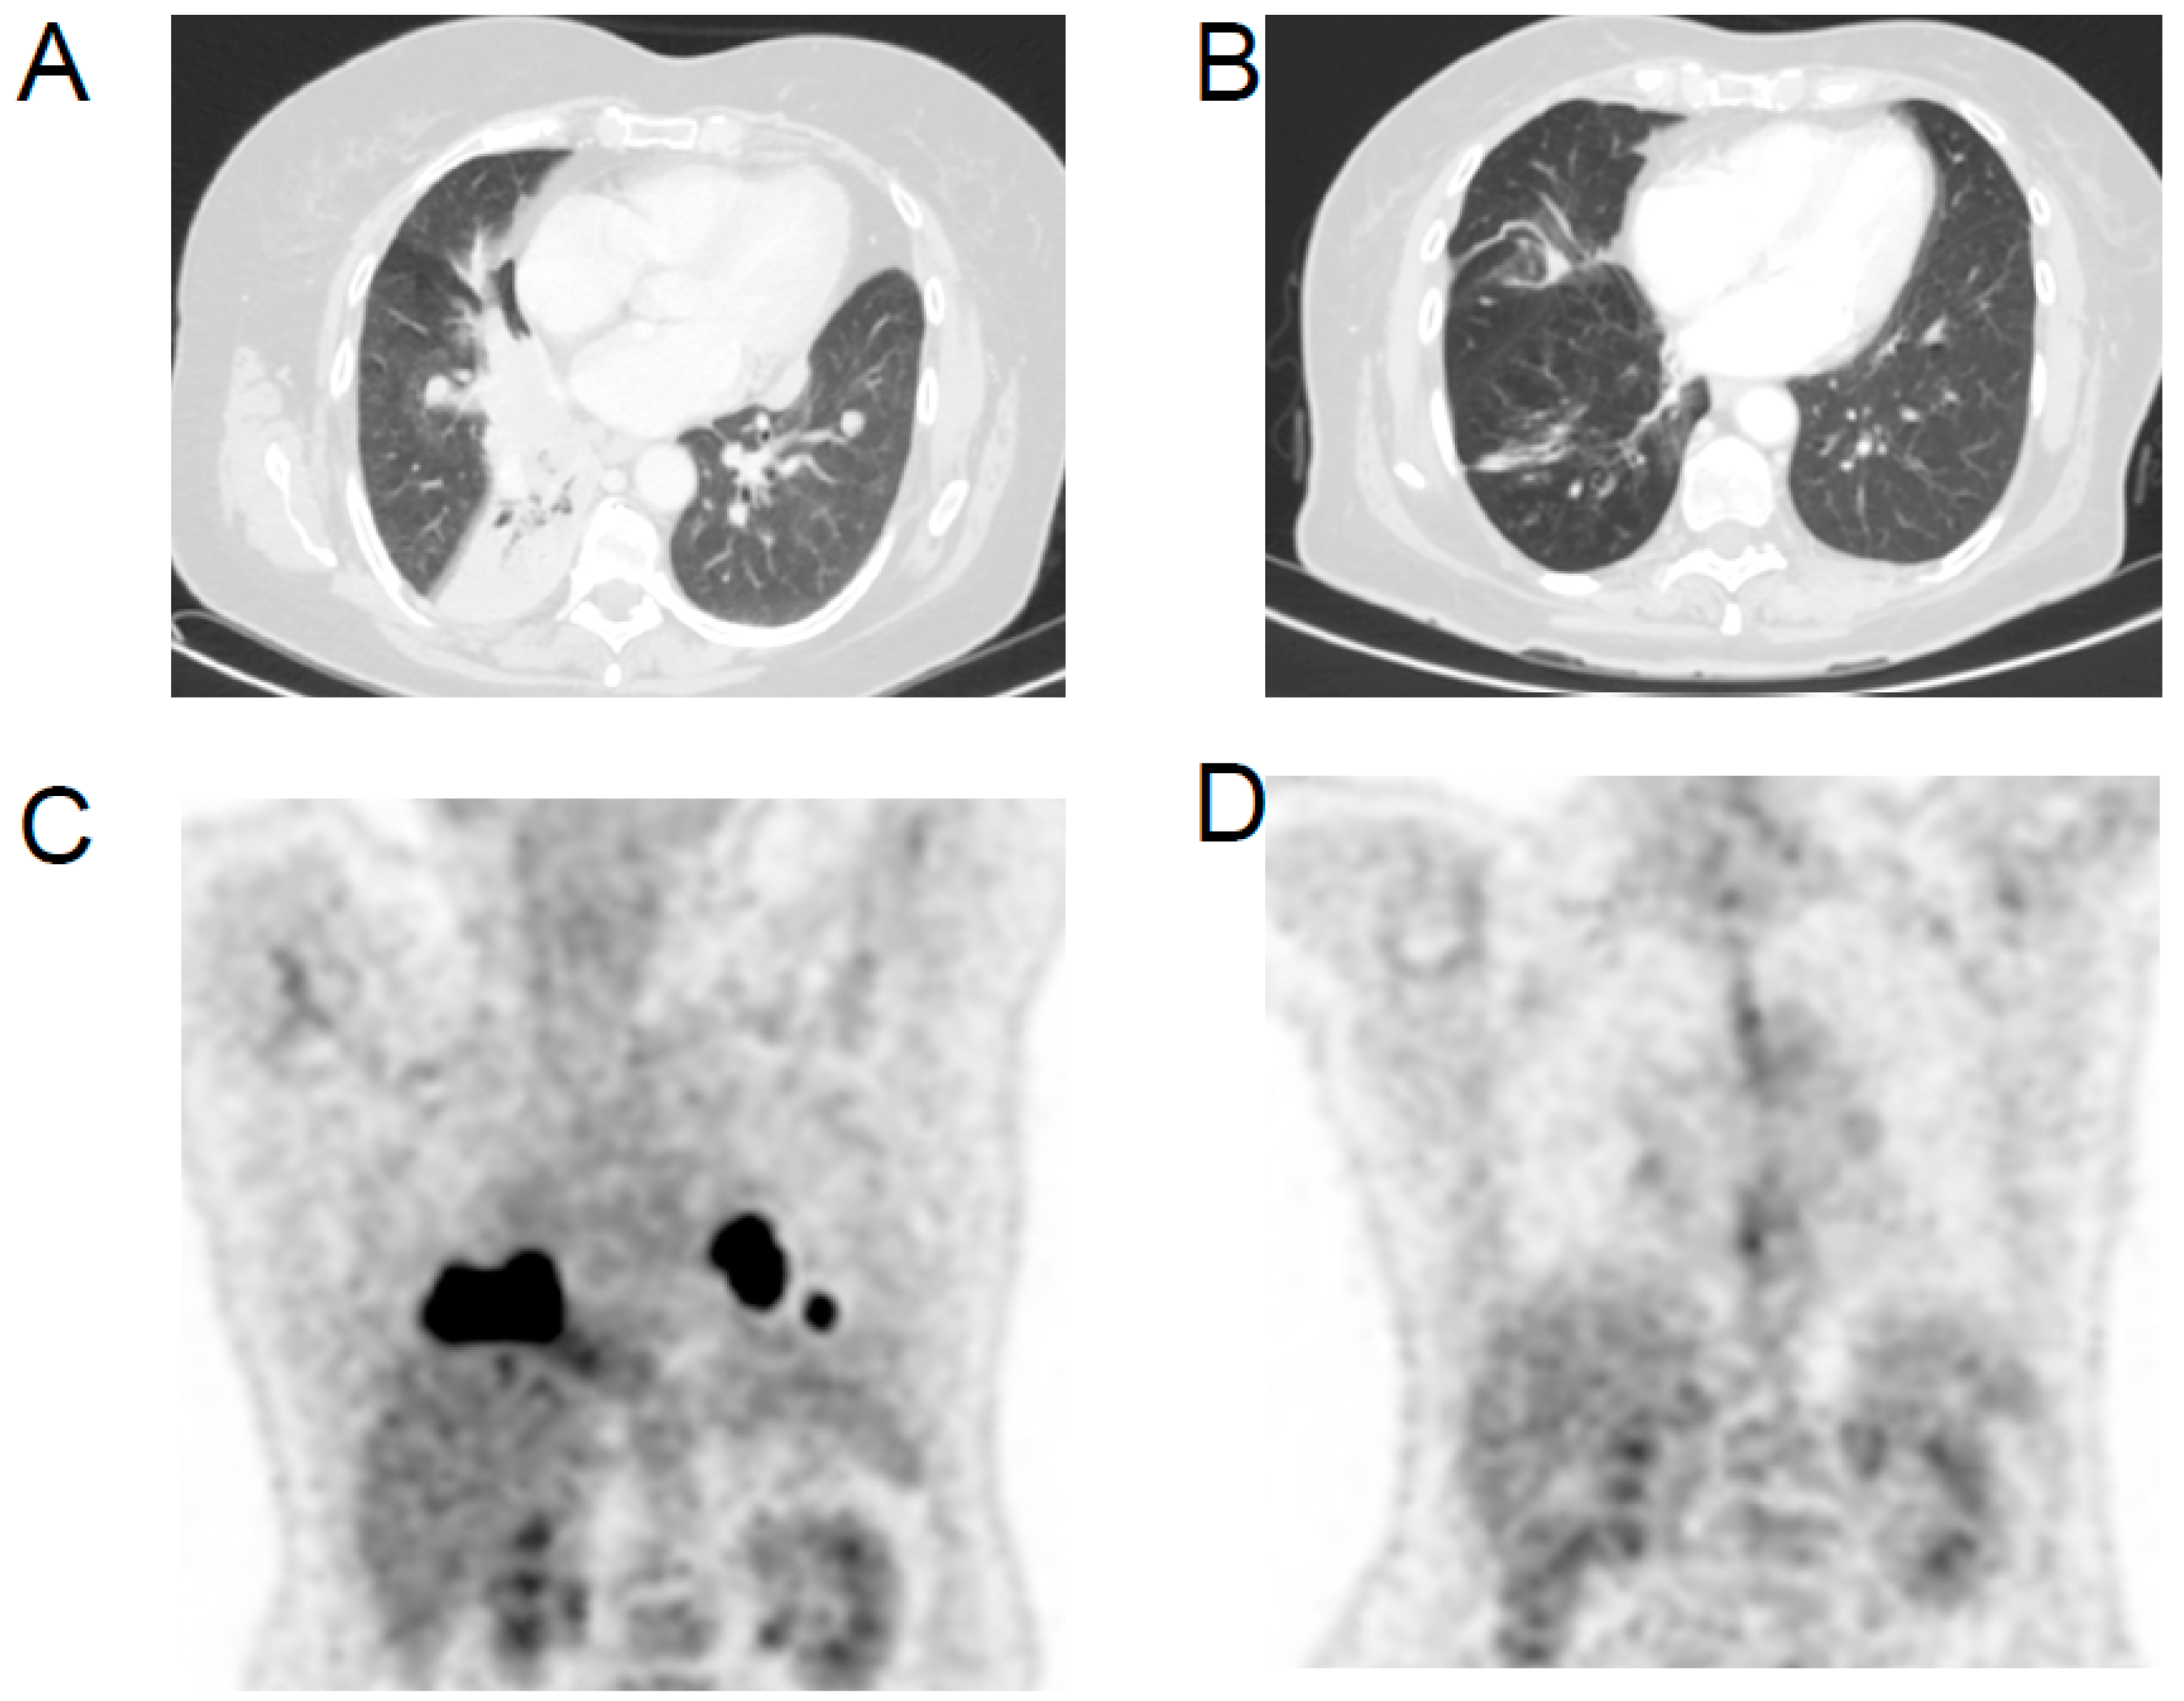

2. Case Report